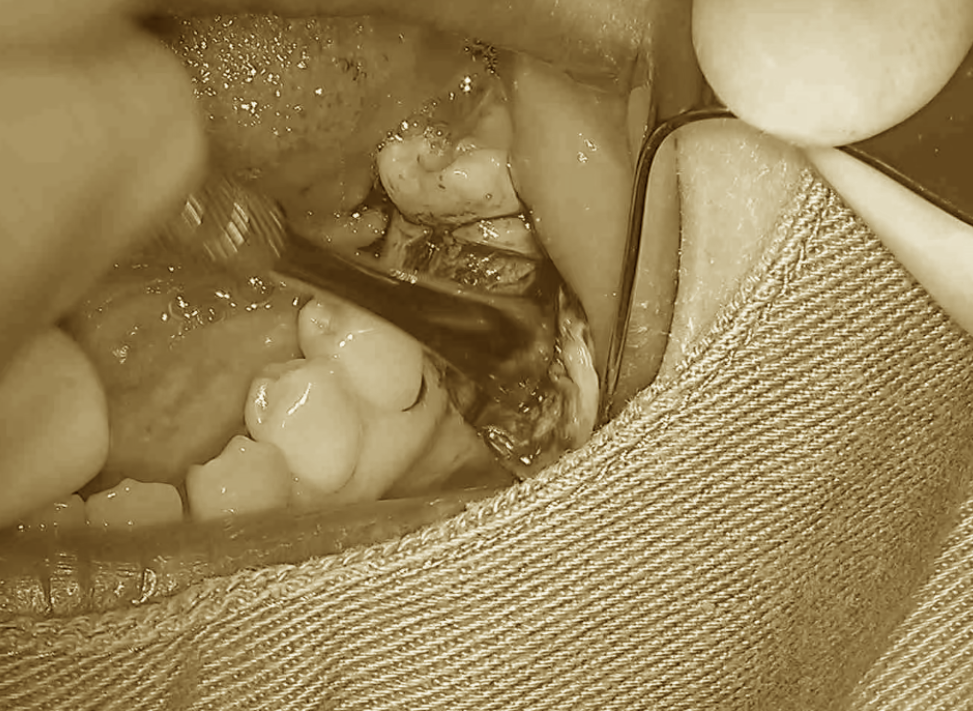

歯の移植をいう選択肢〜手術編Ⅲ〜

前回に引き続き、手術の続きをご紹介していきます。

移植床の形成がおおよそのサイズまで整った段階で、歯牙レプリカを用いて適合の確認を行います。

この時点では、まだ完全にはフィットしていないため、再度細かい調整を加えていき…